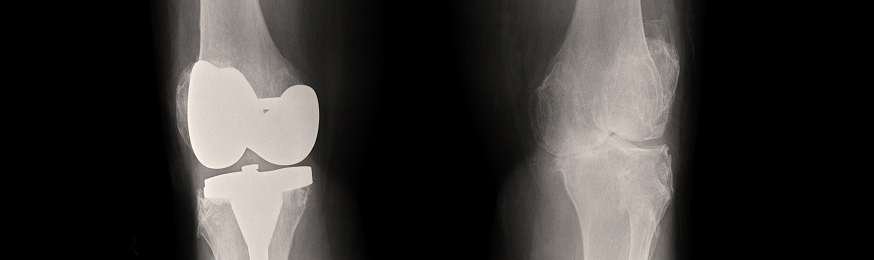

According to the FDA, the DePuy LPS Diaphyseal Sleeve is to be used with the LPS System – an end-stage revision knee product that allows surgeons to reconstruct severe soft tissue and bony defects. The device is manufactured by DePuy Orthopaedics, Inc., which is a subsidiary of Johnson & Johnson. The FDA says the diaphyseal sleeve should enhance the fit and fill of the diaphyseal femoral canal with femoral and tibial replacements.

However, the FDA says, the sleeve-to-sleeve base taper connection may not be sufficient enough to accommodate potential physiologic loads during normal movements by some patients. In turn, the sleeve may fracture at the taper joint, possibly leading to a loss of function or loss of limb, infection, compromised soft tissue or – in the worst cases – death.